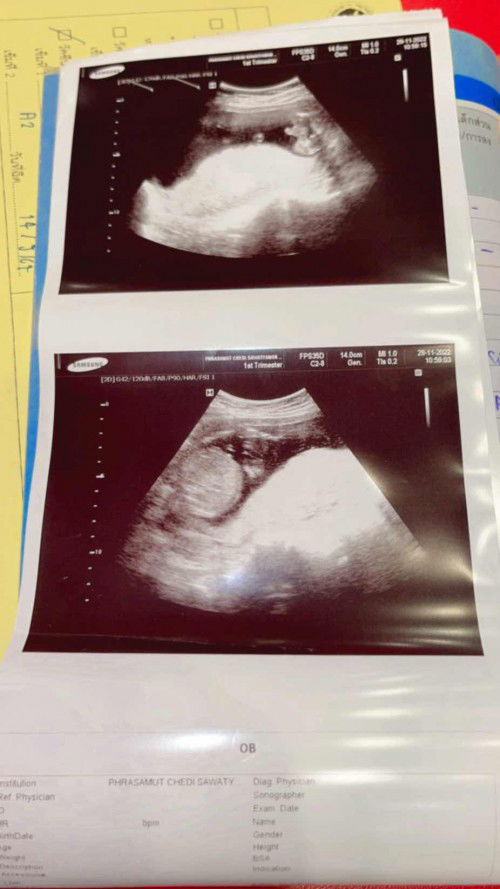

ช่วยดูเพศหน่อยได้ไหมค่ะ หมอบอกน้องมีจู๋ แต่ที่แม่เห็นมันเหมือนขามากเลยค่ะ

ไปซาวด์มารอบที่แล้วตอนอายุครรภ์ 18w4d หมอบอกจู๋น้องโผล่มาเลยค่ะ แต่แม่ยังไม่แน่ใจเลย ใจจริงอยากได้ลูกสาวค่ะ แต่พ่ออยากได้ลูกชาย แต่เราดูยังไงก็เหมือนขาน้องเลยค่ะ

จู๋ค่ะแม่ 🤣 รูปข้างบนชี้ชัดเลยค่ะ